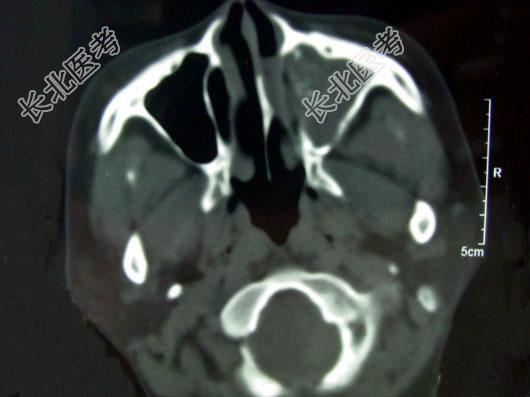

- 单项选择题男,41岁, 左侧鼻腔胀痛半年余,CT检查如图, 最可能的诊断是 ( )

A、出血坏死性息肉

B、化脓性鼻窦炎

C、过敏性鼻窦炎

D、真菌性鼻窦炎

E、上颌窦癌